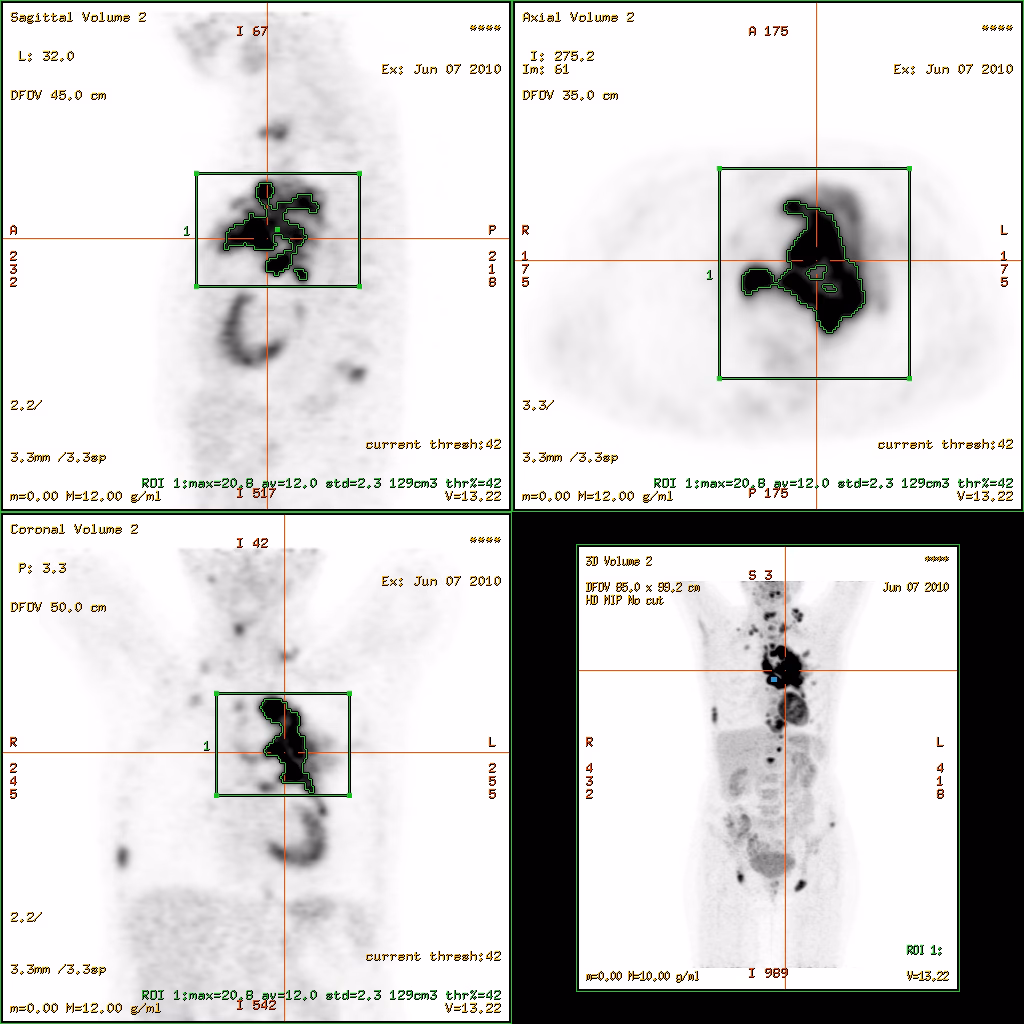

Læger ser ofte på flere forskellige SUV-målinger for at få det fulde billede af en tumors aktivitet. De mest almindelige er SUVmax, SUVmean og SUVpeak.

- SUVmax: Repræsenterer den absolut højeste værdi målt i en enkelt pixel inden for det interessante område. Den er nem og hurtig at måle, men kan være følsom over for billedstøj.

- SUVmean: Er gennemsnitsværdien af alle pixels inden for det afgrænsede tumorområde. Den giver et indtryk af den samlede aktivitet, men er meget afhængig af, hvordan radiologen præcist definerer tumorens grænser.

- SUVpeak: Beregnes som et gennemsnit over en lille, standardiseret volumen i den mest aktive del af tumoren. Denne måling er designet til at være mere robust og mindre følsom over for støj end SUVmax.

Mens SUV måler intensiteten af den metaboliske aktivitet, fortæller den ikke hele historien. To patienter kan have tumorer med samme SUVmax, men den ene tumor kan være meget større end den anden. Derfor er man i stigende grad begyndt at anvende volumetriske parametre, der kvantificerer den samlede sygdomsbyrde.

- Metabolisk Tumorvolumen (MTV): Dette er et mål for det samlede volumen af den metabolisk aktive tumor i kroppen. Det svarer på spørgsmålet: "Hvor meget aktiv kræft er der?"

- Total Læsion Glykolyse (TLG): Dette er et samlet mål, der kombinerer både volumen og intensitet. Det beregnes ved at gange MTV med SUVmean.